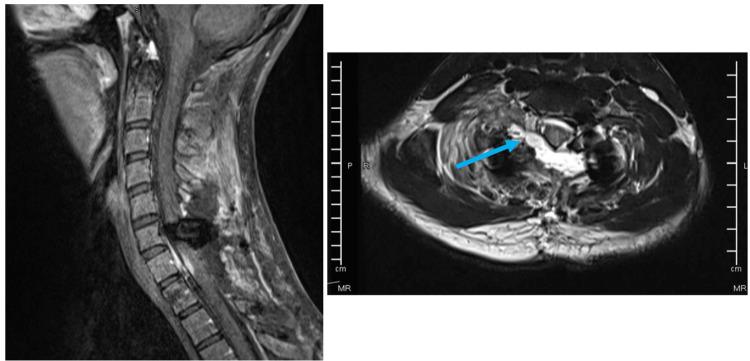

Ewing sarcoma is a rare neoplasm that mostly grows in bones or soft tissues around bones. Most cases of Ewing sarcoma occur in intra-skeletal locations (long bones, pelvis, or ribs) and rarely in extra-skeletal regions such as paravertebral or epidural space, whereas a primary intradural extramedullary Ewing sarcoma (IEES) is extremely rare. Fifty cases of primary IEES including our case were identified in the literature, so far, of which two-thirds are in the lumbosacral region, while only 12 reports described a cervical location of the tumor. Herein, we are presenting a case of C7-T1 primary IEES for a 24-year-old male, followed by a review of updated literature about the primary IEES in the cervical spine.

尤因肉瘤是一种罕见的肿瘤,主要生长于骨骼或骨骼周围的软组织。大多数尤因肉瘤病例发生于骨骼内部(长骨、骨盆或肋骨),很少发生于椎旁或硬膜外间隙等骨骼外区域,而原发性硬脊膜内髓外尤因肉瘤(IEES)极为罕见。迄今为止,文献中已报道了包括我们的病例在内的50例原发性IEES病例,其中三分之二位于腰骶部,而仅有12篇报道描述了肿瘤位于颈椎。在此,我们报告一例24岁男性C7-T1原发性IEES病例,并对颈椎原发性IEES的最新文献进行综述。